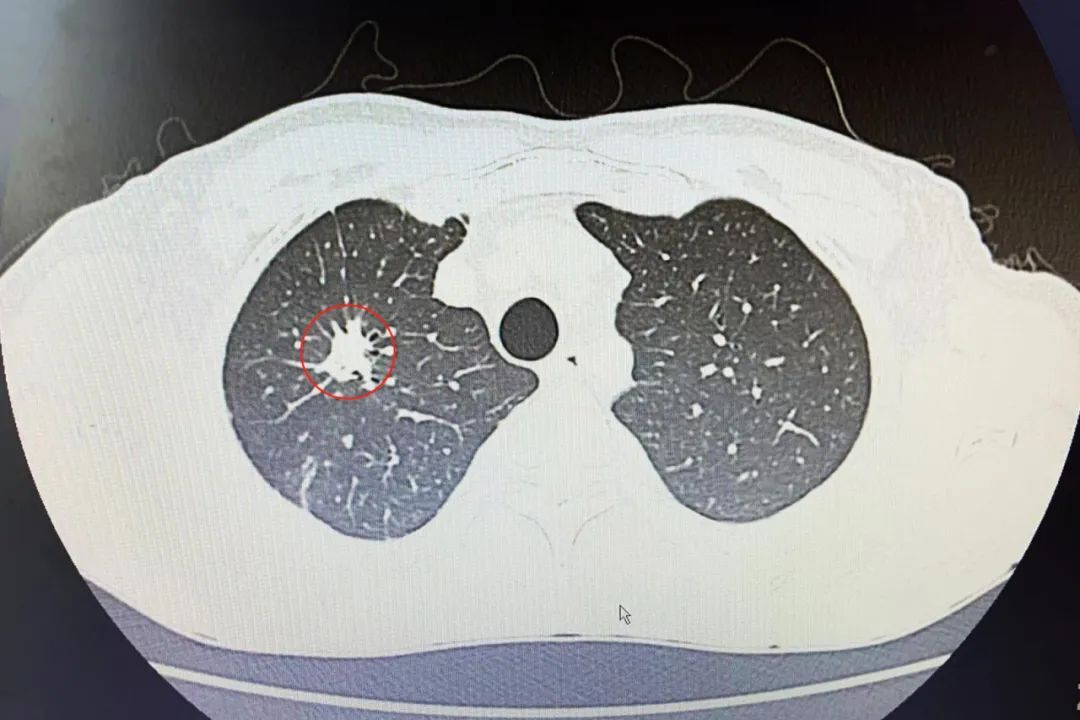

病例右肺上叶后段不规则软组织肿块影周围可见毛刺及条索影

【病例】右肺上叶后段不规则软组织肿块影,周围可见毛刺及条索影.